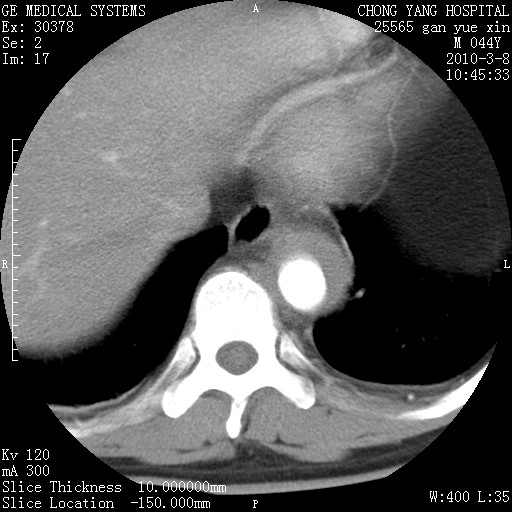

标题: CT24940:主动脉增强,典型病例。 [打印本页]

标题: CT24940:主动脉增强,典型病例。

夹层动脉瘤。

动脉夹层

夹层动脉瘤,典型

主动脉夹层。

动脉夹层的分型:

⒈debakey分型:根据主动脉夹层累及部位,分为三型:ⅰ型:原发破口位于升主动脉或主动脉弓部,夹层累及升主动脉、主动脉弓部、胸主动脉、腹主动脉大部或全部,少数可累及髂动脉。ⅱ型:原发破口位于升主动脉,夹层累及升主动脉,少数可累及部分主动脉弓。ⅲ型:原发破口位于左锁骨下动脉开口远端,根据夹层累及范围又分为ⅲa,ⅲb。ⅲa型:夹层累及胸主动脉。ⅲb型:夹层累及升主动脉、腹主动脉大部或全部。少数可累及髂动脉。

⒉stanford分型:a型:夹层累及升主动脉,无论远端范围如何。b型:夹层累及左锁骨下动脉开口以远的降主动脉。

夹层动脉瘤,少量胸水

夹层动脉瘤;左侧少量胸腔积液。

典型主动脉夹层。